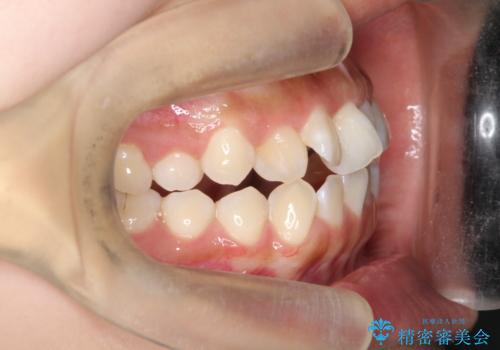

- 患者様は、上の前歯に翼状捻転(歯が回転して生えている状態)があり、全体の歯並び(叢生)の改善を希望して来院されました。診断の結果、非抜歯での治療が可能であると判断し、上顎にリンガルアーチを装着し、矯正用アンカースクリューを併用することで臼歯部を確実に遠心移動させる治療計画を立案しました。これにより、スペースを確保しつつ、前歯をきれいに並べることを目指しました。